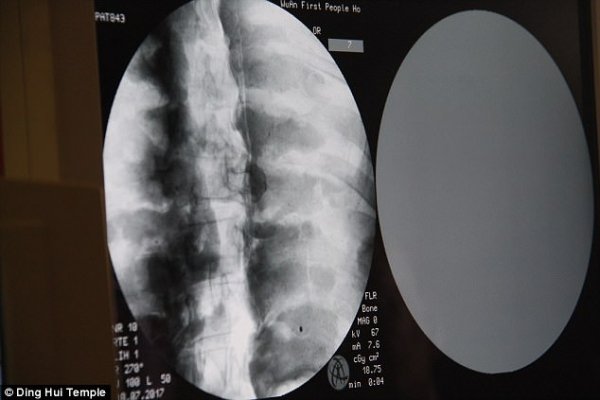

但是經過千年大家才知道這尊佛像裏頭的卻是....根據了解有研究學者透過X光還有XT掃描檢驗,發現驚人的秘密!這是貨真價實的木乃伊,但沒想到最難保存的大腦竟然都還留著!?

當地學者受訪表示:「我們在掃描後發現,他的骨頭跟一般人的一樣完整。」

「上額、上面的牙齒、肋骨、脊椎骨、連關節全部都還在。真的是很驚奇的景象」